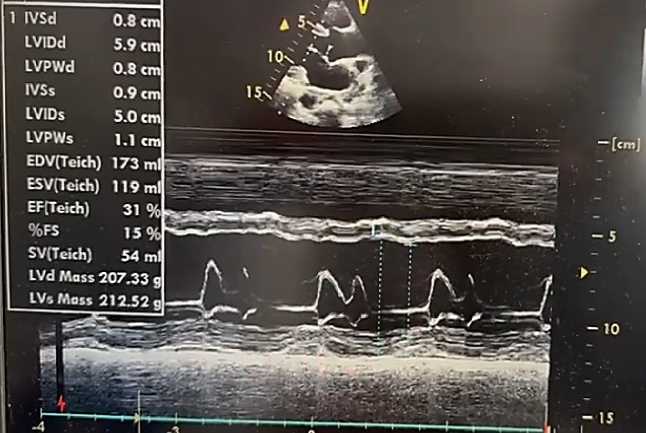

Эхокардиография. По данным ультразвукового исследования сердца у пациента А., 38 лет: толщина межжелудочковой перегородки — 0,9 см, задней стенки левого желудочка (ЛЖ) — 0,9 см. Фракция выброса ЛЖ (по Симпсону) — 38%. Размер левого предсердия — 4,5 см. Конечный систолический размер ЛЖ — 4,2 см, конечный диастолический размер ЛЖ — 6,1 см. Конечный систолический объём ЛЖ — 72 мл (референс: 18–68 мл), конечный диастолический объём ЛЖ — 168 мл (референс: 59–157 мл). Размер правого желудочка — 2,2 см, толщина его передней стенки — 0,4 см. Систолическое давление в лёгочной артерии — 32 мм рт. ст. Выявлены диффузный гипокинез миокарда ЛЖ, снижение систолической функции и нарушение процессов диастолического расслабления. Полости левых отделов сердца расширены. Перикард — без патологических изменений (Рисунок 2, 3, 4). Отмечены признаки атеросклеротического поражения аорты, аортального и митрального клапанов. Допплерографическое ультразвуковое исследование сонных и бедренных артерий: кровоток сохранён, признаков структурных и функциональных нарушений не выявлено. При обследовании венозных сосудов верхних и нижних конечностей тромбоз не диагностирован.

Рисунок 3. Эхокардиография пациента А., 38 лет с миокардитом. В М-режиме графическое движение стенок сердца и створок клапанов во времени / оценка систолической функции желудочков